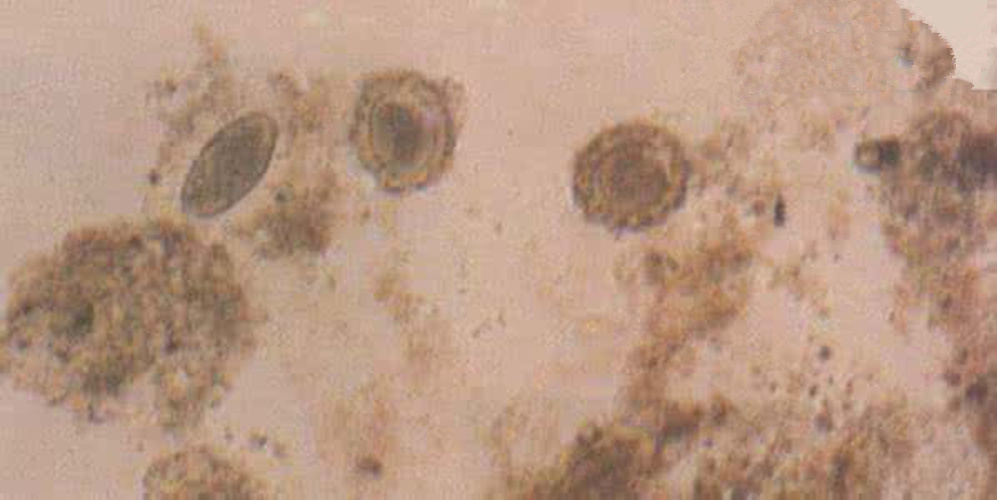

腸絛蟲病圖片

蛔蟲病症狀診斷